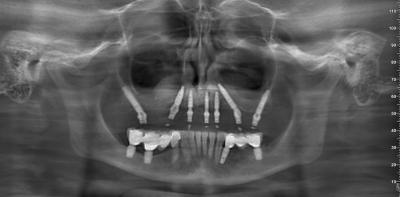

Базальна імплантація зубів, ціна якої в Ali’s Premium Dental Care приємно здивує, передбачає установку опор у кортикальні, більш щільні відділи кістки. Саме тому базальний імплант стабільно фіксується навіть за вираженої атрофії або після тривалого носіння знімних протезів. Рішення доцільне, коли втрачено багато зубів, спостерігається рухомість через пародонтальні проблеми, є обмеження часу на лікування, потрібна опора під незнімний міст без тривалих підготовчих етапів. У «Алі Дентал» показання підтверджуються КТ-діагностикою та цифровим плануванням – це зменшує ризики та робить етапи зрозумілими.

У пацієнтів з тонким альвеолярним гребенем, зональною атрофією або після травм базальна технологія допомагає формувати опорний каркас без кісткових підсадок у багатьох сценаріях. Водночас остаточне рішення приймають після оцінки щільності кістки, стану слизової, звичок у харчуванні та якості гігієни – так прогноз стає реалістичним.

Лікування в клініці Ali Dental складається з узгоджених кроків. Спершу проводять КТ, цифрові відбитки, моделювання прикусу й естетики. Далі йде хірургічний етап – установка опор під анестезією з контролем позицій. За показаннями можлива рання фіксація тимчасового мосту, що допомагає швидше повернути жування і дикцію. Наступний блок – примірки й остаточне протезування з перевіркою фонетики й стабільності оклюзії.

Базальна імплантація зубів призначається при множинних втратах, атрофії кістки, довготривалому використанні знімних протезів, локальних дефектах після травм або видалень. Метод сумісний з більшістю клінічних ситуацій, у тому числі коли потрібна тотальна реабілітація щелепи. Тимчасові обмеження можливі за гострих запалень слизової, декомпенсованих системних станів чи активного куріння – у таких випадках спершу стабілізують фон, далі узгоджують навантаження. В Ali’s Premium Dental Care тактика пояснюється просто: пацієнт розуміє, чому обрано саме цей сценарій і як виглядатимуть етапи.